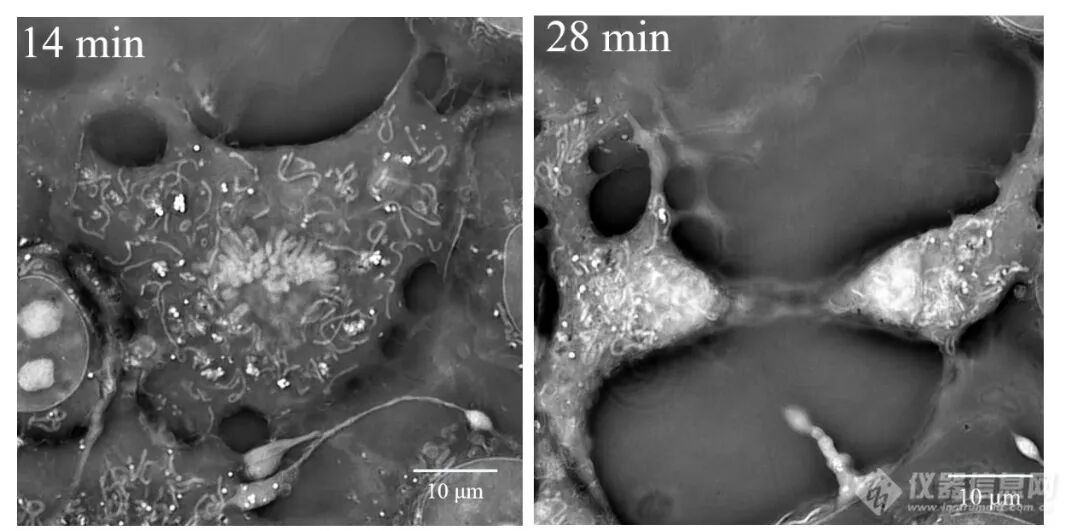

在线粒体动力学与药物评估研究中,使用SC3000无需标记即可清晰捕捉线粒体融合与分裂事件,并直观呈现顺铂等药物诱导的线粒体碎片化、肿胀等早期毒性表型(图7a),以及保护药物干预后的形态修复全过程(图7b),从而实现对药物作用机制的直观、量化评价。

计算光学驱动的新一代显微革命:无标记光强衍射层析赋能活细胞与类器官三维成像

图7a   顺铂(CDDP)作用后,线粒体肿胀并碎片化